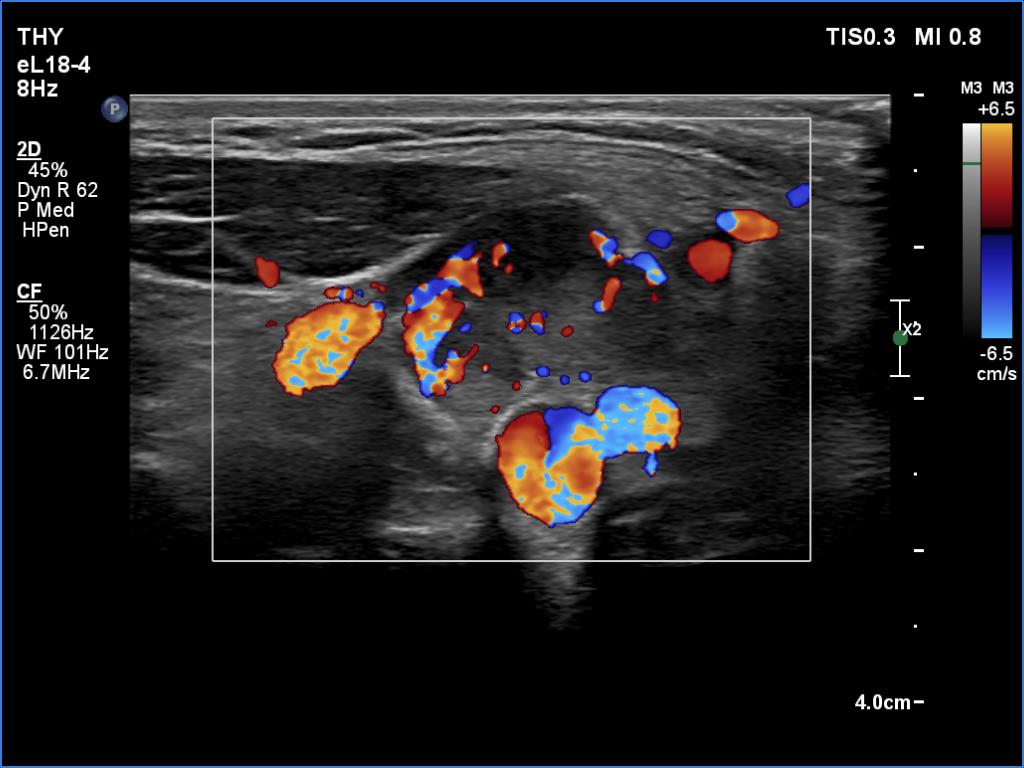

Ultrasonography. The thyroid was hypoechoic. The right lobe had a heterogeneous, dominantly minimally/moderately hypoechoic nodule in the ventrolateral part which had irregular borders and both perinodular and intranodular vascularity. There was another, hyperechoic star-like lesion in the central part of the right lobe. This lesion presented microcalcifications and was avascular. The left lobe was homogeneously hypoechoic.

According to the palpable mass in the right submandibular area, there was a heterogeneous lesion which has hypoechoic and echonormal parts. The mass had irregular margins and showed vascularity. The distance between the submandibular mass and the thyroid was more than 35 mm.